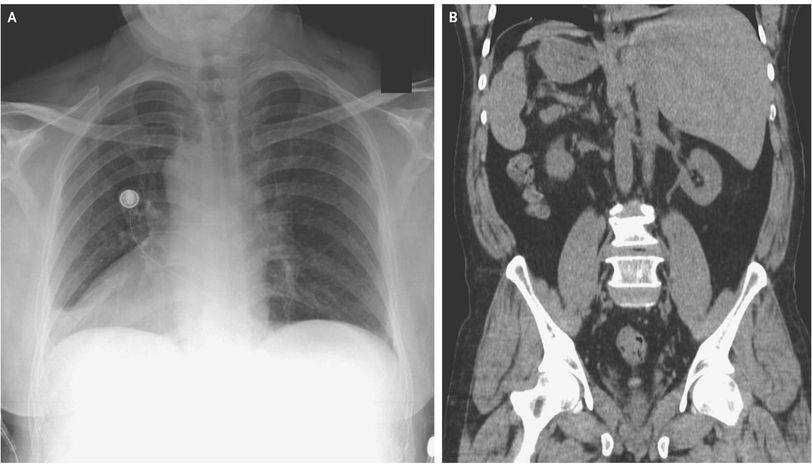

Situs Inversus Totalis is a congenital condition in which the positions of the left and right sided organs are reversed. In such people, the heart beats on the right side! Other organs such as liver and spleen are also present on the other side of the body, as revealed by the image above. This anomaly may be associated with a defect in ciliary function, thus leading to frequent respiratory infections and infertility. The disease is referred to as the Kartagener’s Syndrome. (Image via: https://www.nejm.org/doi/full/10.1056/NEJMicm1811002 )